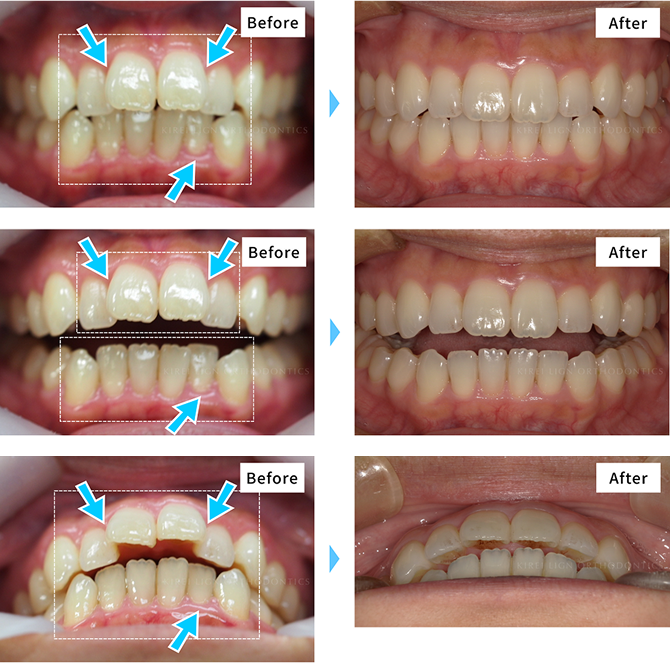

矯正治療の症例

対応する症例

キレイラインは

部分矯正に特化したものから

- ガタガタした

歯並びや八重歯 - すきっ歯

- 出っ歯(上顎前突)

- 前歯が閉じない

(開咬※1) - 中心が

ズレている※2 - 噛み合わせが深い

- 受け口※3

- ※上記の歯並びであっても、キレイライン矯正が適応外となる場合もございます。

- ※1:骨格性の開咬の場合は、治療適応外となります。

- ※2:骨格的な問題がなくても、お口の状況によっては「中心のずれ」を治すことは難しい場合があります。「中心のずれ」にはさまざまな原因があり、ワイヤー矯正など他の矯正治療においても一般的にその修正は困難な場合があります。

- ※2,※3:症状が強い場合は適応にならない場合があります。